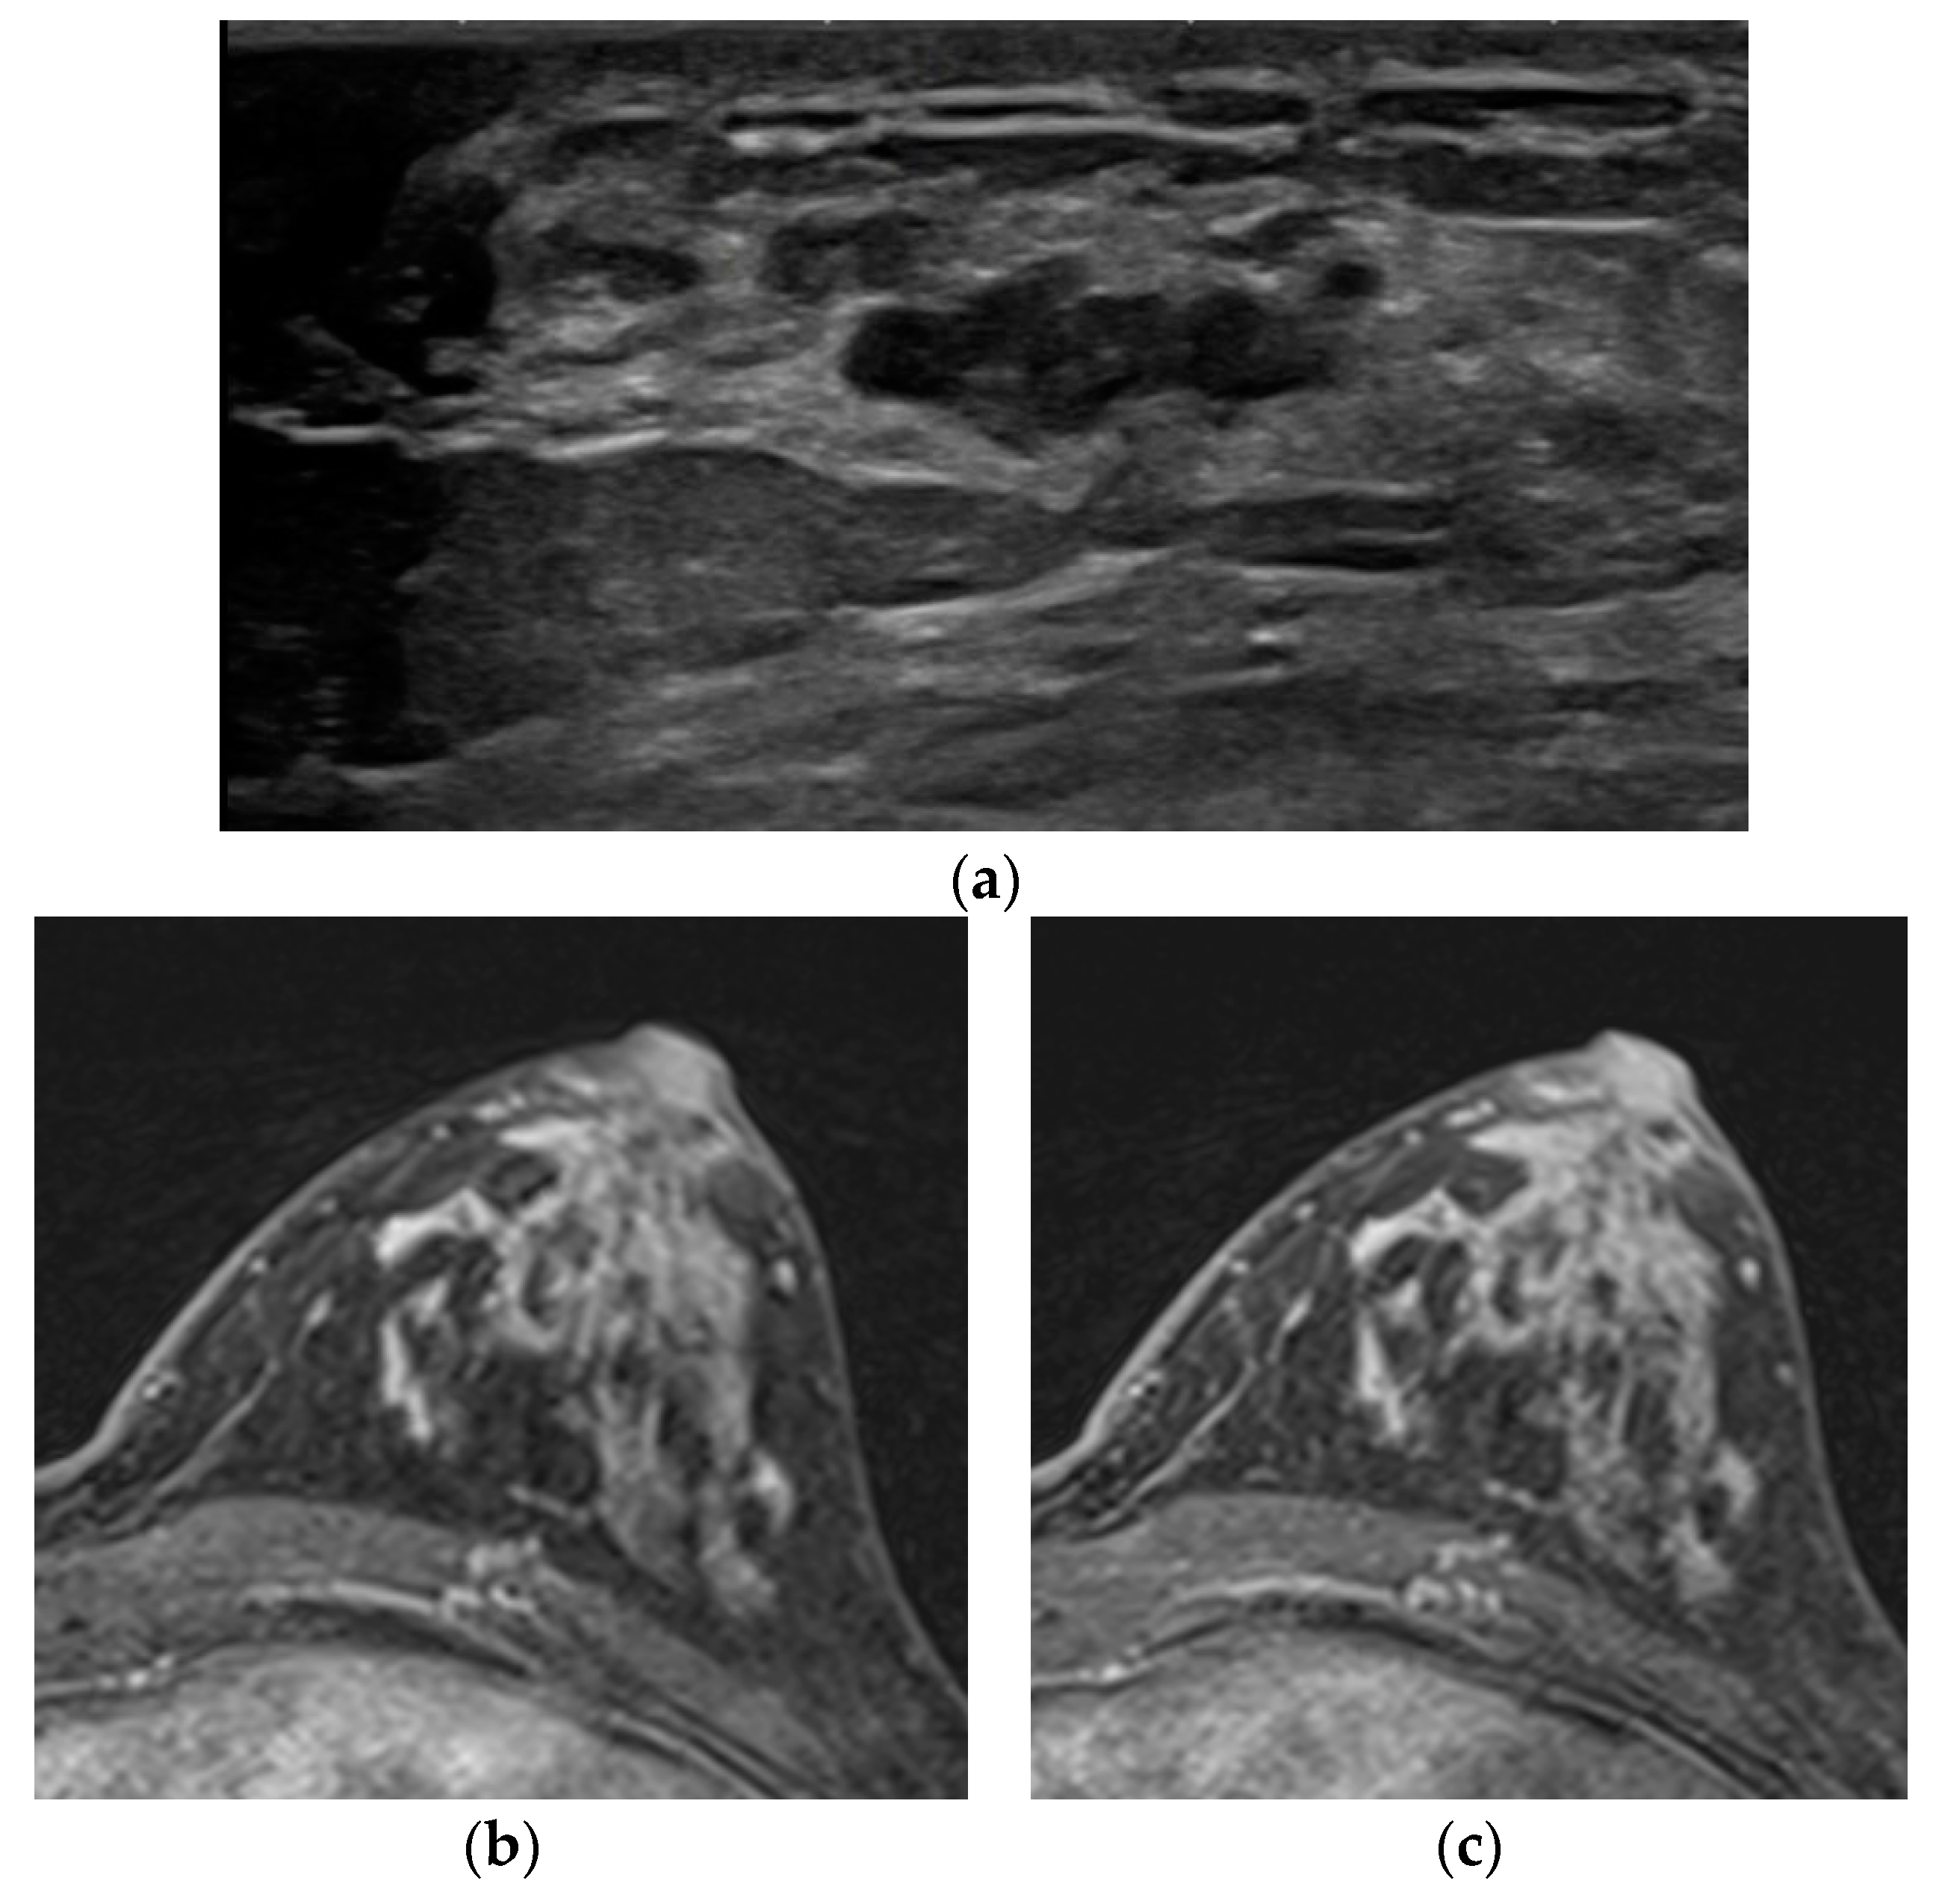

Figure 3. A 53-year-old woman with screening. (a) In the ultrasound, a 2 cm irregular hypoechoic mass was detected in the left breast in the 3-o’ clock direction and confirmed as invasive ductal carcinoma with ductal carcinoma in situ. The final pathology revealed 0.5 cm-sized invasive cancer with 2.4 cm-sized DCIS. No discernible lesion was identified in the subtraction image from the early phase (b) or the delayed phase of T1WI due to the marked level of BPE (c).

The other case was a patient who complained of a growing palpable mass at the far upper breast with a history of injection mammoplasty. At first, there was no enhancing lesion at the palpable site, but there was a mass with definite diffusion restriction. The MR re-examination was performed with the prone position considering the location of the palpable site, and an irregular mass with heterogeneous enhancement was confirmed (No. 7). In three cases (Nos. 10–12), lesions could not be distinguished in DCE MR due to marked levels of BPE. Further, lesions were not distinguished in both T2WI and DWI but were identified in ultrasound or mammography (Figure 3).

The last one is the marked level of BPE. BPE is well known as a factor that increases the recall rate and false positive rate in breast MR readings. In particular, if the BPE is at a marked level, it may be almost impossible to distinguish the lesion from the breast parenchyma [21]. In the three cases, lesions were masked by the marked level of BPE in DCE MR; neither T2WI nor DWI was helpful in lesion identification. Conventional imaging, such as mammography or ultrasound, was more valuable. As an approach to minimize the effect of BPE, it is proposed to consider the menstrual cycle [22] or to add an ultrafast sequence [23].